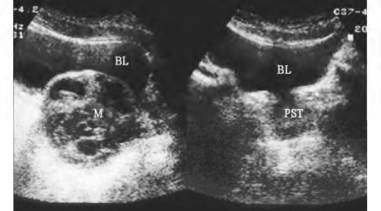

图31-3 精囊腺肿瘤声像图

左图为精囊腺囊实性包块,右图为同一患者前列腺

1.一侧精囊肿大,形态失常,内部失去正常条索状结构(图31-3)。

2.精囊肿瘤显示精囊边界模糊不清,并出现相应部位肿瘤图像;精囊囊肿示精囊一部分或全部为无回声区,囊壁薄,后方回声加强。